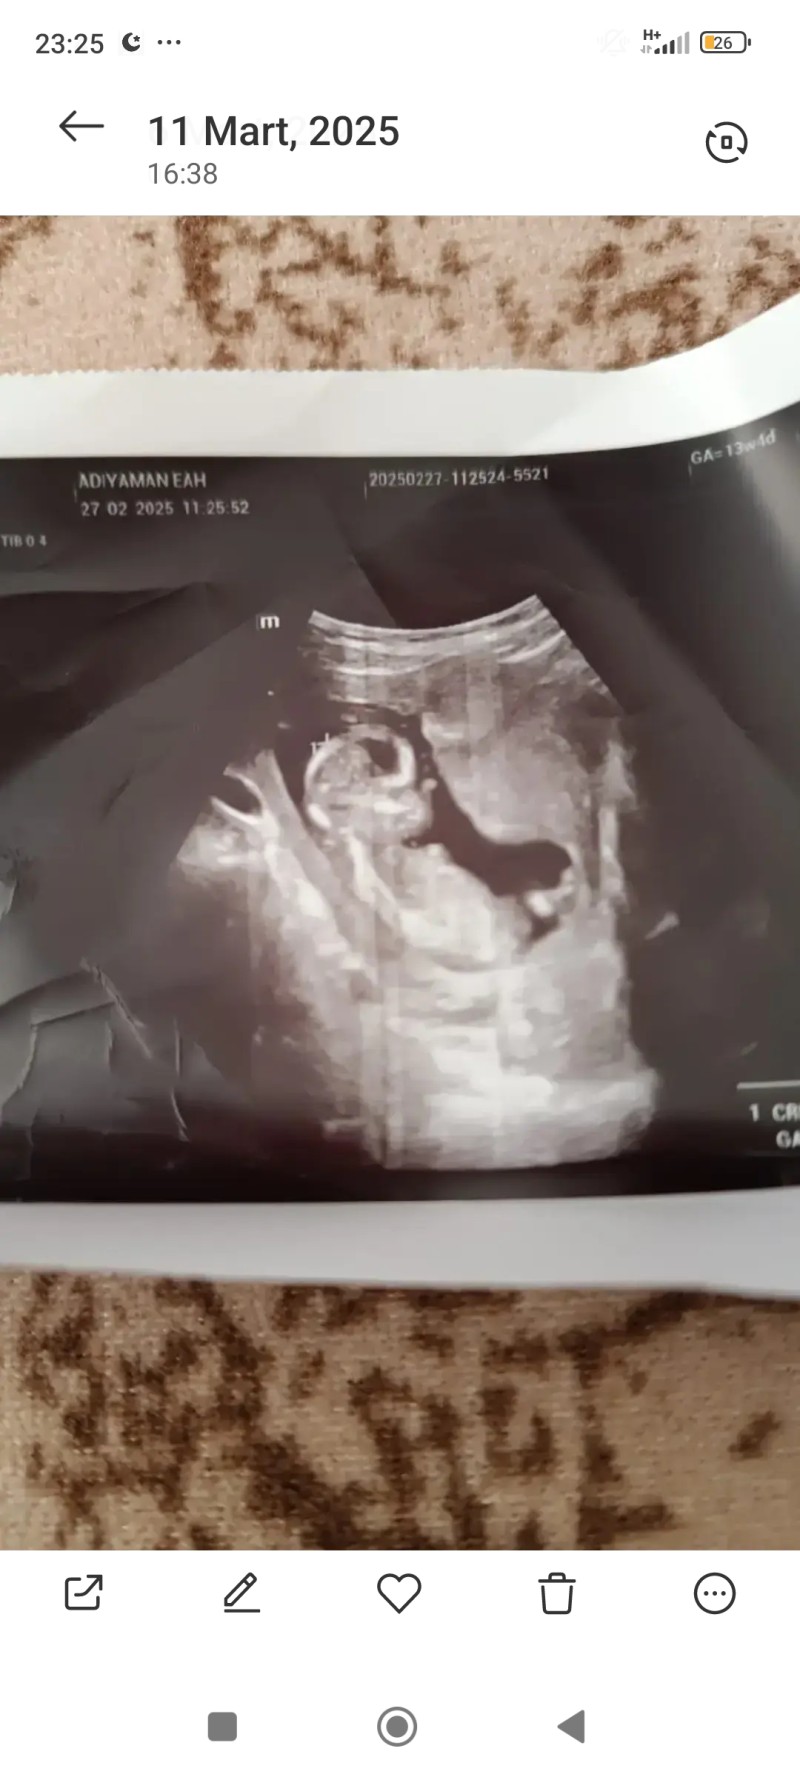

• Cinsiyet tahmini yapalir mısınız hanımlar

image

Erkek .bacak bölgesi yokmu

Bir önceki ultrason kağıdında var

Erkek.....

Farketmez benim için sağlıklı olsun yeter geçen ay erkek demişti bu defa gittiğimde kız dedi benimde kafam karıştı